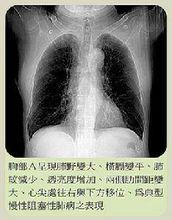

慢性阻塞性肺炎阻塞性肺氣腫的診斷,尤其是早期診斷較不易,應結合病史、體徵、胸部X線檢查及肺功能檢查綜合判斷。凡有逐漸加重的氣急史,肺功能測驗示殘氣及殘氣/肺總量增加,第一秒用力呼氣量/用力肺活量減低,最大通氣量降低,氣體分布不勻,彌散功能減低;經支氣管擴張劑治療,肺功能無明顯改善,診斷即可成立。